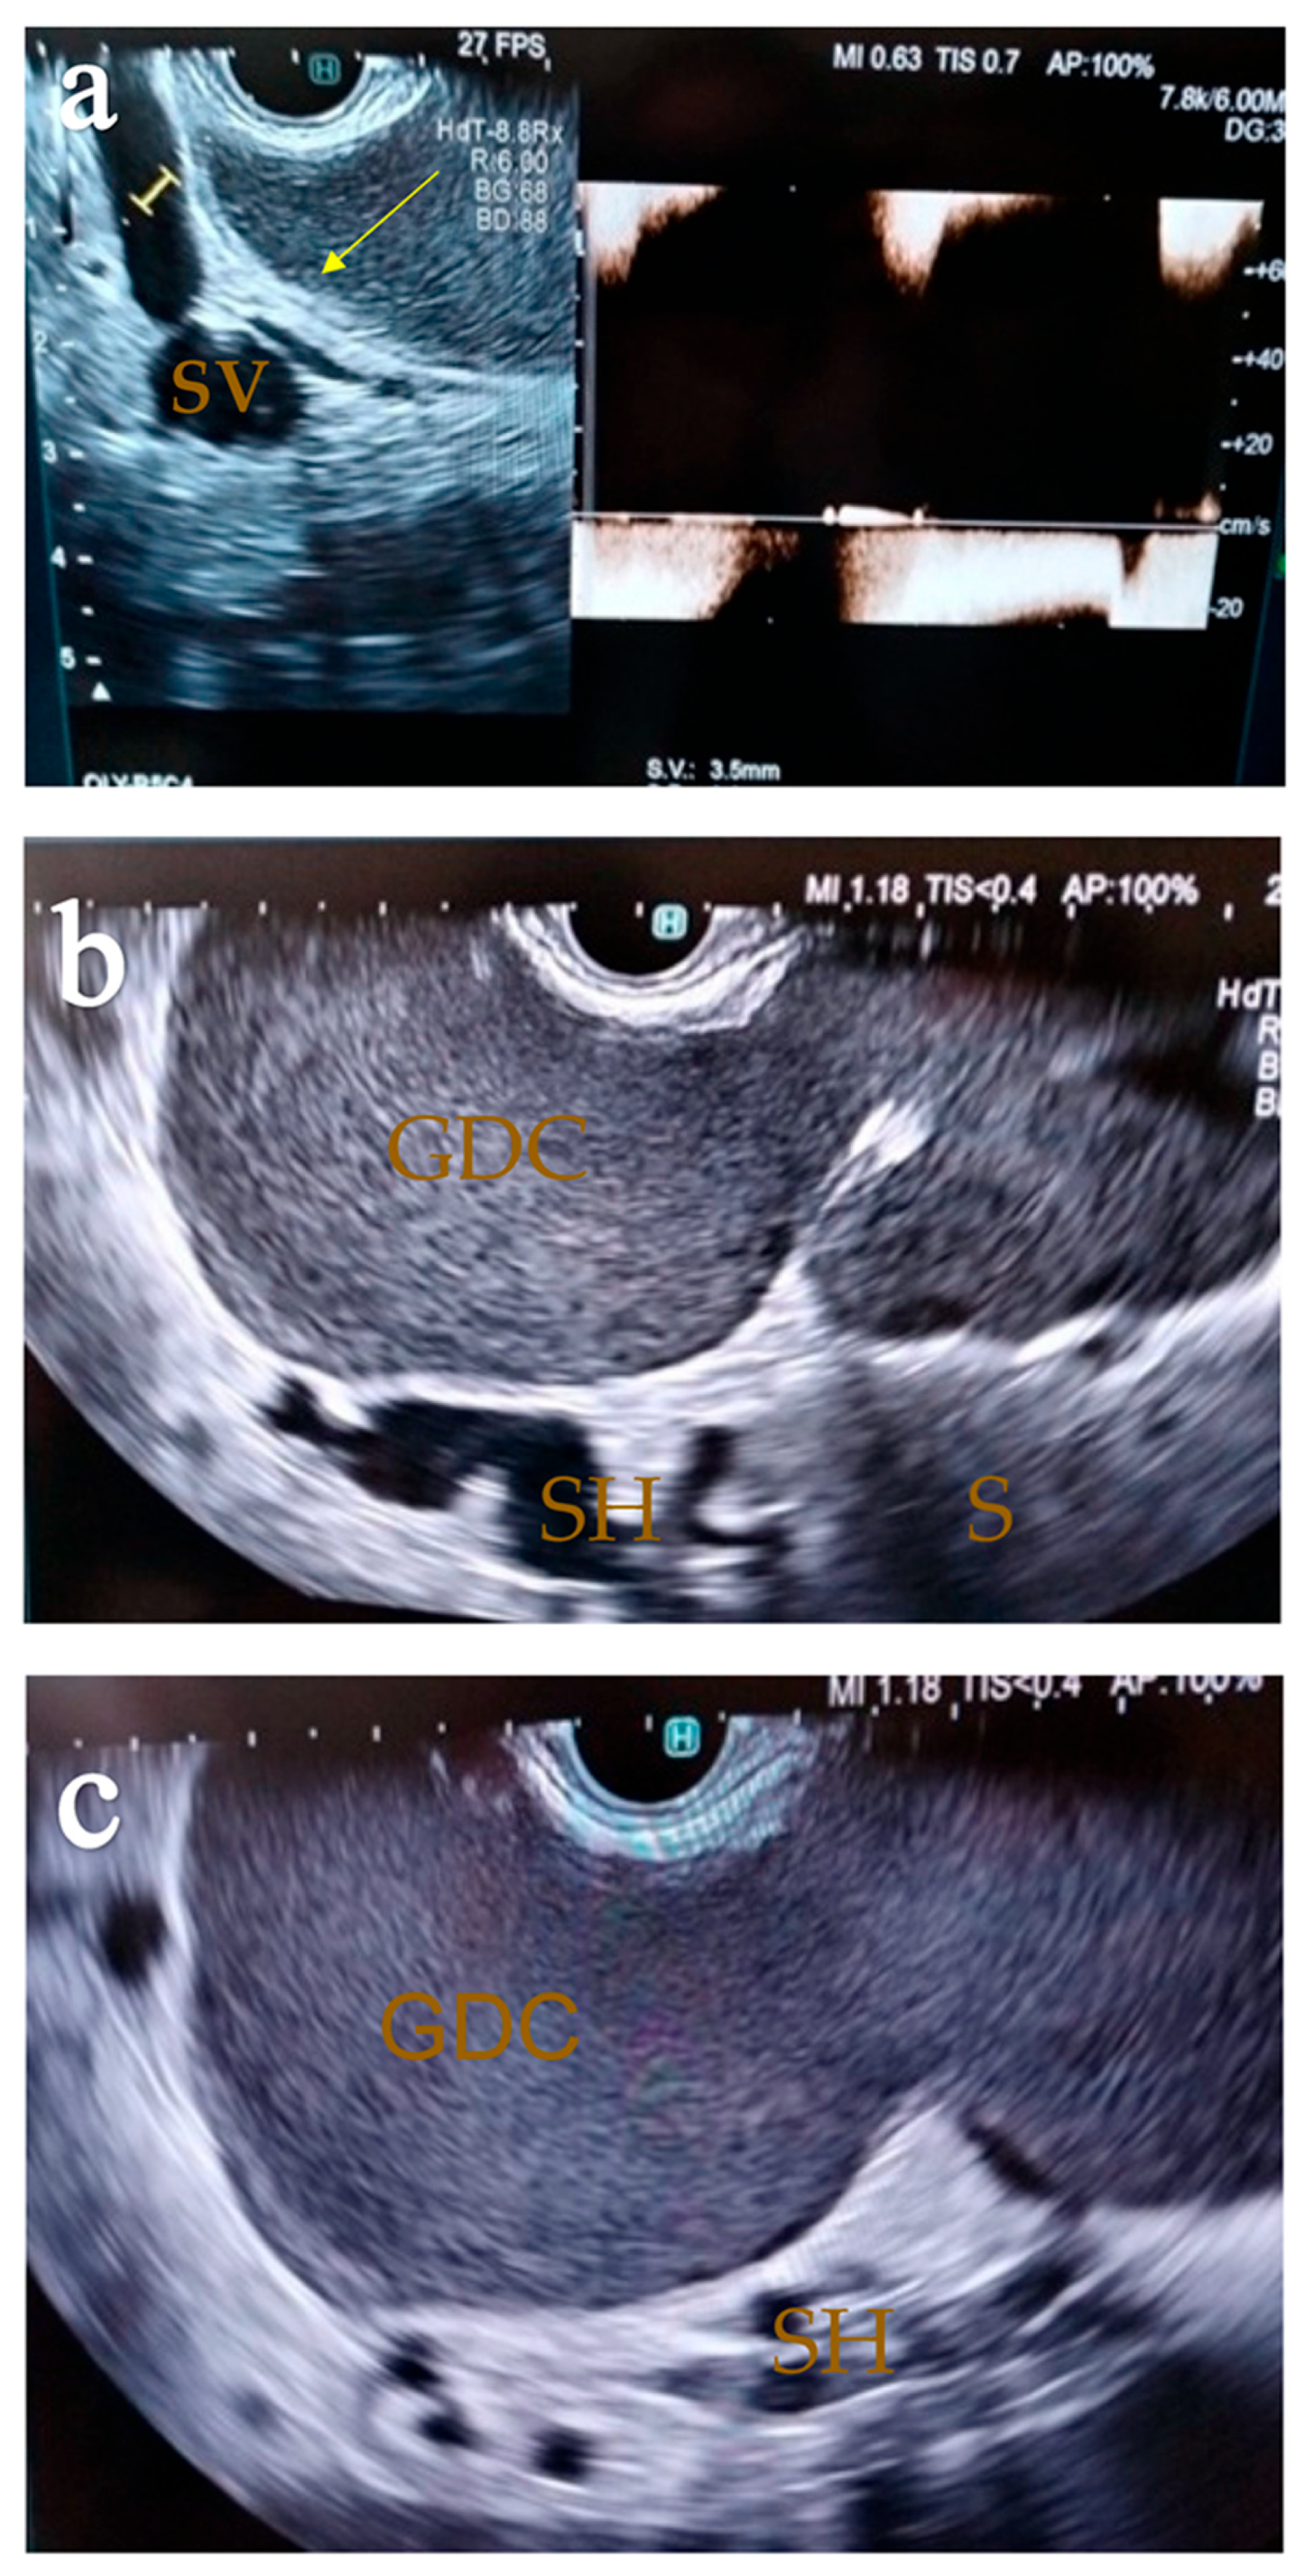

2. Case Report